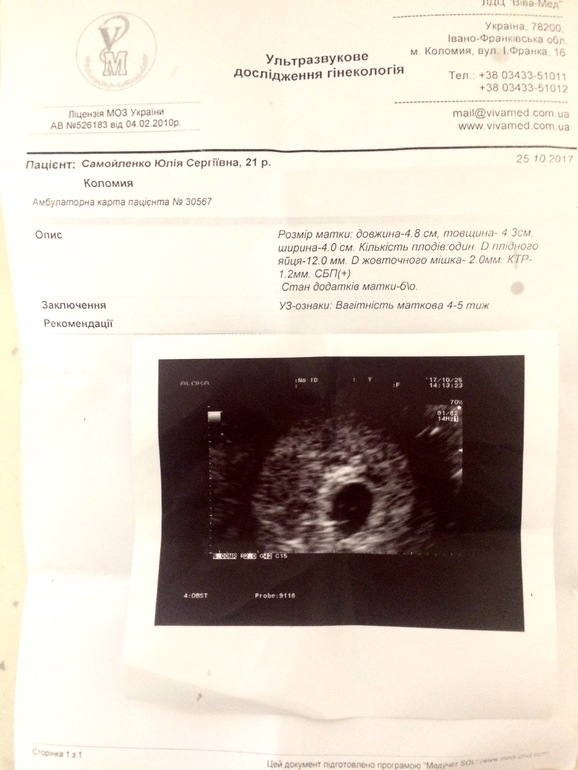

12. Первое УЗИ (срок): 4-5 недель ПЯ-12.0 ММ,КТР 1.2ММ СБП +![]()

Овуляция была 2 октября, месячные должны были начаться 16-17 октября. От овуляции примерно до 4 недель. А от месячных то получается до 6 недель. ПЯ 12 мм. Я незнаю почему они написали 4-5 недель в заключении, думаю это эмбриональные.